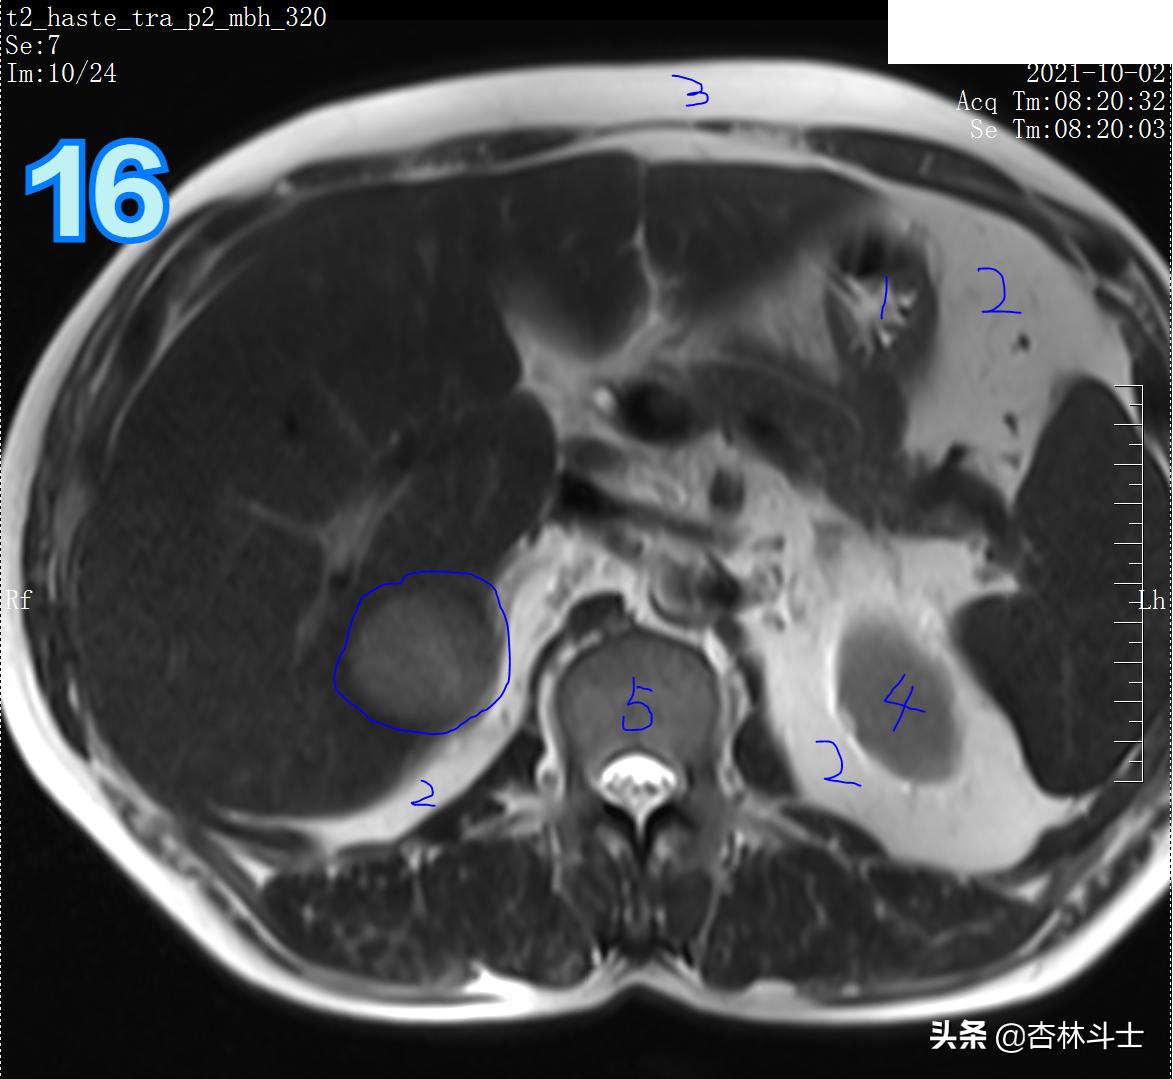

T2加权像

图16 1、胃腔 2、腹腔及腹膜后脂肪组织 3、皮下脂肪 4、左肾 5、腰椎椎体 蓝框为病灶。

T2

图17 1、胃 2、脾 3、左肾肾周脂肪 4、双侧膈肌脚 5、椎间盘 6、椎管